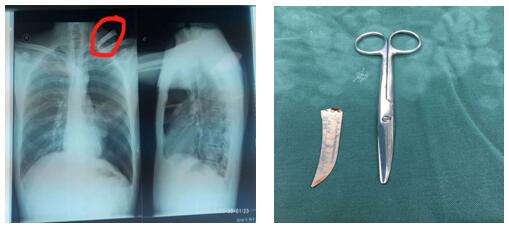

患者左頸根部可見一長約2cm傷口,邊緣整齊,內(nèi)插入刀片斷端出血不止。左頸根部刀刺傷常常會損傷頸胸部大血管導(dǎo)致大出血危及生命、同時會造成開放性氣胸危及生命,病情非常危急,需行急診開胸探查術(shù)。苗主任與李偉主治醫(yī)師、李仁栓主治醫(yī)師立即制定了手術(shù)方案。1:40分患者被送進(jìn)手術(shù)室,在全麻下行胸腔鏡探查楔形切除、肋間血管縫合,胸壁傷口清創(chuàng)術(shù)。手術(shù)緊張有序地進(jìn)行。凌晨4點(diǎn)鐘患者安全返回病房,手術(shù)順利完成。從患者頸部取出的刀片長約10cm 左右。